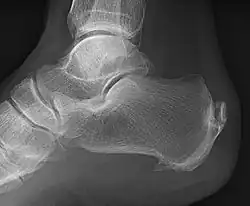

| A radiograph showing osteophytes on the posterior and inferior aspects of the calcaneus | |

An inferior calcaneal spur is located on the inferior aspect of the calcaneus and is typically a response to plantar fasciitis over a period, but may also be associated with ankylosing spondylitis (typically in children). A posterior calcaneal spur develops on the back of the heel at the insertion of the Achilles tendon.[3]

An inferior calcaneal spur consists of a calcification of the calcaneus, which lies superior to the plantar fascia at the insertion of the plantar fascia. A posterior calcaneal spur is often large and palpable through the skin and may need to be removed as part of the treatment of insertional Achilles tendonitis.[3]